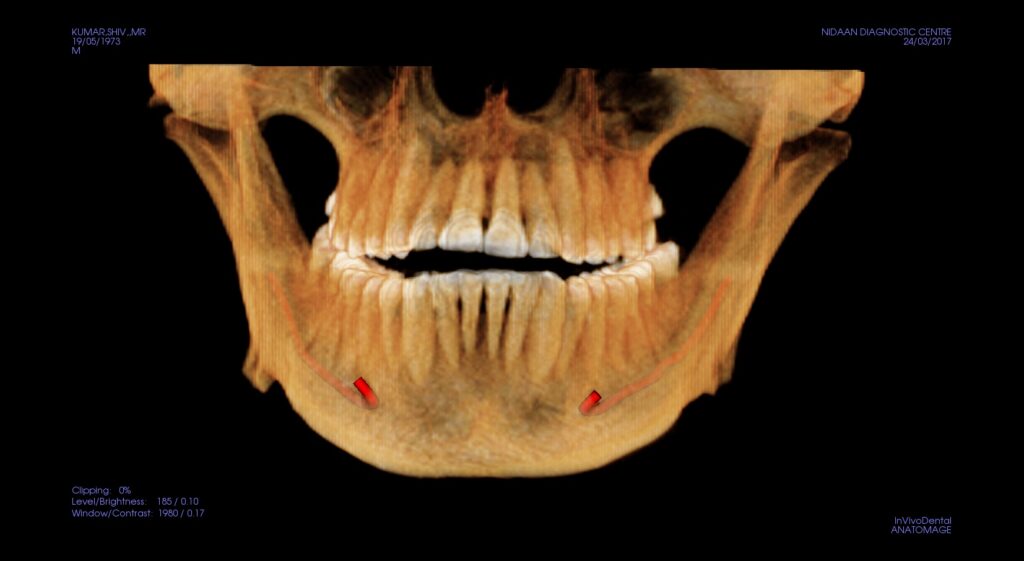

Pre-Implant Assessment

Advanced 3D Visualization